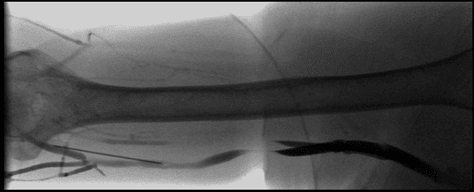

En intervencionista se usa el soporte de la fluoroscopia para los accesos venosos. Inicialmente se utilizaba el método por flebografía y posteriormente se introdujo la ecografía.